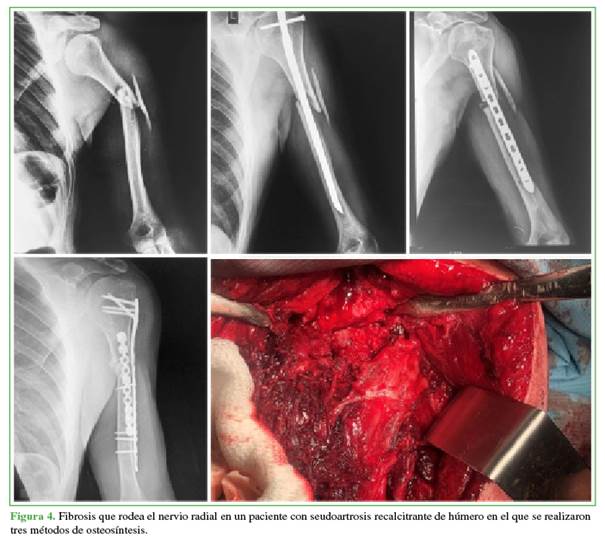

La distribución de estos nueve casos de parálisis posoperatoria fue: siete por cirugías primarias (6 operados tras fracturas agudas y 1 por consolidación viciosa) y dos por reoperaciones (1 por seudoartrosis y 1 por pérdida de la reducción de una fractura aguda) (Figura 4). Los nueve pacientes referían hipoestesia en el territorio sensitivo del nervio radial.

La seudoartrosis y la consolidación viciosa se produjeron luego de la osteosíntesis con placa recta y un abordaje transtricipital.